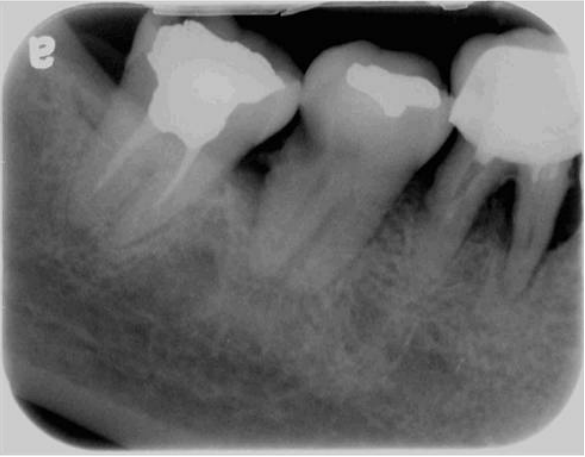

9.42歲女性患者主訴右下後牙區在喝冷水時有劇烈抽痛的現象,其X光片如下圖所示。造成患者主訴疼痛的牙齒與病因來源為 何? (A)第一大臼齒的牙髓病變 (B)第一大臼齒的根尖周圍病變 (C)第二大臼齒的牙髓病變 (D)第二大臼齒的根尖周圍病變